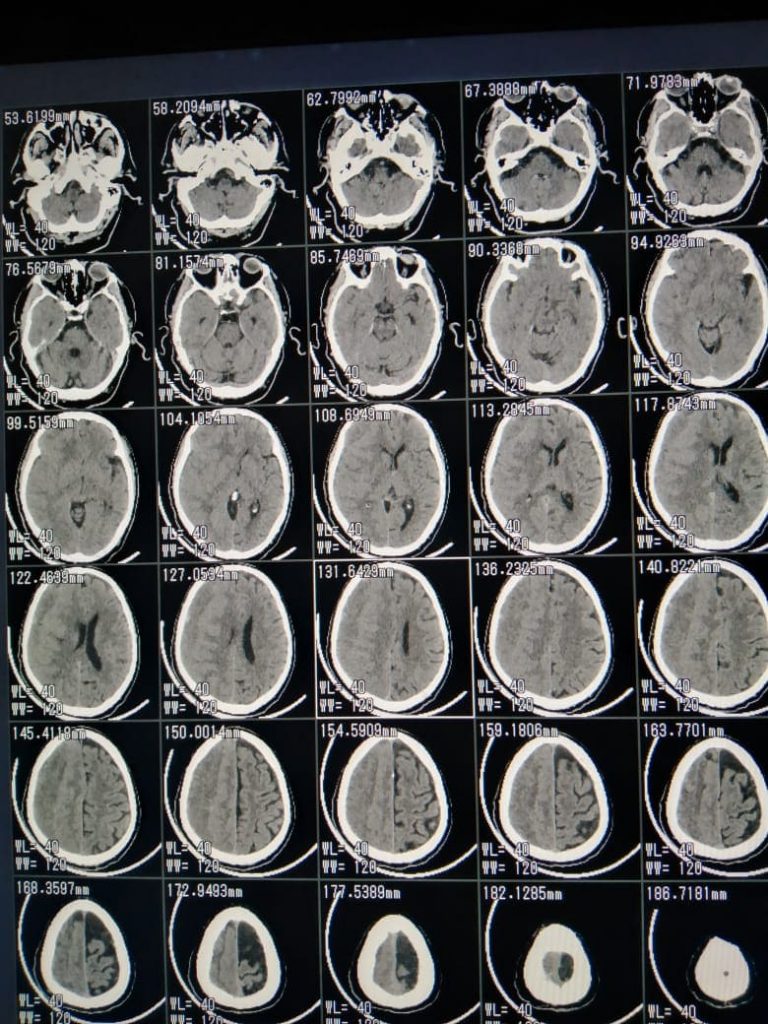

أعلن الدكتور هشام شوقي مسعود وكيل وزارة الصحة بالشرقية بقيام الفريق الطبي بقسم جراحة المخ والأعصاب بمستشفي الزقازيق العام بمشاركة الدكتور وائل المسلمي، والدكتور السيد صباح محمد، والدكتور عماد عبد القادر، وهيئة التمريض بقسم العمليات، قاموا اليوم الجمعة 16 إبريل 2021 بإجراء جراحة دقيقة بالمخ لمسجون يعاني من شلل نصفي تام بالجانب الأيسر نتيجة تجمع دموي بالمخ، وذلك بعد توقيع الكشف الطبي علي المريض وإجراء كافة الفحوصات الطبية والأشعات اللازمة له، والتنسيق بين قطاع السجون ومديرية الشئون الصحية لإجراء الجراحة الدقيقة للمريض، وتوفير كافة أوجه الرعاية الطبية له، وتمت العملية الجراحية بنجاح والحالة الآن مستقرة وتحت الملاحظة الطبية، بإشراف مدير المستشفي.